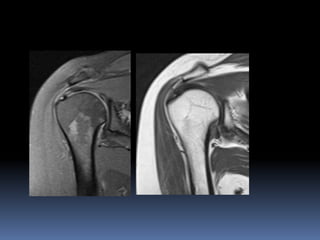

Anterior middle

posterior